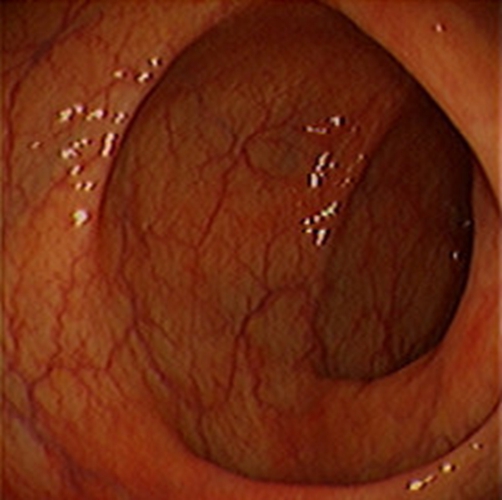

急性胃炎圖片

急性胃炎陽性表現

急性胃炎陽性的表現的

急性胃炎陽性的表現

急性胃炎陽性表現的

急性胃炎的陽性的表現的

急性胃炎的陽性的表現